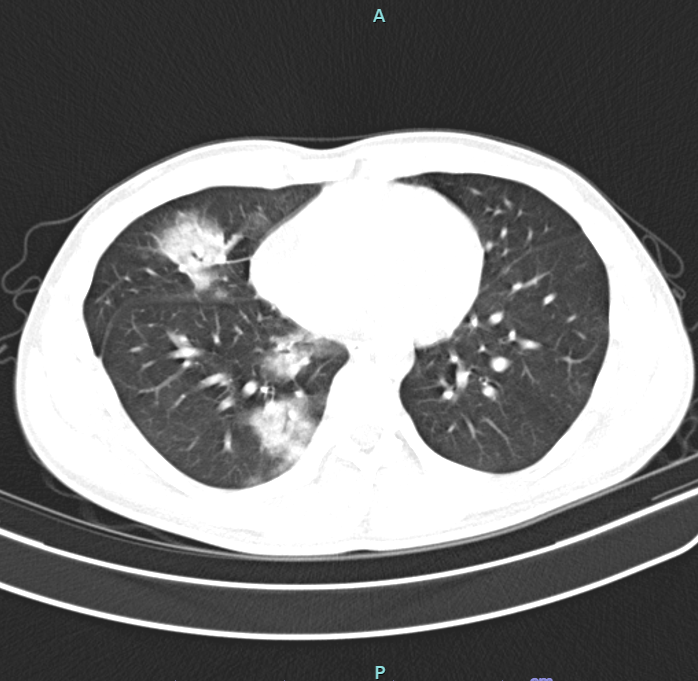

Người bệnh được chỉ định xét nghiệm máu, đờm, chụp phim cắt lớp vi tính ngực, trên phim chụp cắt lớp vi tính ngực, tổn thương thâm nhiễm rộng thùy dưới phổi phải. Người bệnh được Chẩn đoán viêm phổi, nguyên nhân ban đầu nghĩ đến do hút thuốc lá điện tử.

Người bệnh được điều trị kháng sinh, long đờm, phục hồi chức năng hô hấp. Sau đợt điều trị, các triệu chứng và tổn thương phổi trên phim có cải thiện, người bệnh tiếp tục được hướng dẫn theo dõi tại nhà và khám lại theo lịch hẹn.

BSCKII, Bùi Mạnh Cường – Trưởng khoa Nội hô hấp (Bệnh viện Đa khoa tỉnh Phú Thọ) cho biết: “Tình trạng của người bệnh diễn biến khá phức tạp. Mặc dù người bệnh còn rất trẻ, không có bất kỳ bệnh lý nền nào nhưng tổn thương ở phổi lại rất nặng nề, không khác gì ở người cao tuổi. Chúng tôi đã phải áp dụng những biện pháp điều trị nhằm bảo tồn tối đa chức năng phổi của người bệnh”.